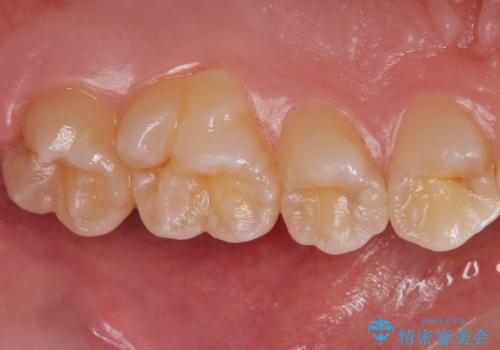

歯と歯の間の虫歯 セラミックインレーでの治療

- 検査の結果、歯と歯の間に大きな虫歯が確認されました。

セラミックでの治療をご希望されたため、セラミックインレーでの治療を行いました。

- 左上45 セラミックインレー 7,7000円×2本 費用は治療当時の料金となります

今回は残せる歯の厚みが十分確保できたため、インレーでの修復処置となりました。